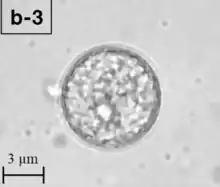

A Balamuthia mandrillaris cyst

B. mandrillaris is a free-living, heterotrophic amoeba, consisting of a standard complement of organelles surrounded by a three-layered cell wall (thought to be made of cellulose), and with an abnormally large cell nucleus. On average, a Balamuthia trophozoite is about 30 to 120 μm in diameter. The cysts fall around this range, as well.[8]

Balamuthia's lifecycle, like the Acanthamoeba, consists of a cystic stage and a non-flagellated trophozoite stage, both of which are infectious, and both of which can be identified in the brain tissue on microscopic examination of brain biopsies performed on infected individuals. The trophozoite is pleomorphic and uninucleated, but binucleated forms are occasionally seen. Cysts are also uninucleated, possessing three walls: an outer thin irregular ectocyst, an inner thick endocyst, and a middle amorphous fibrillar mesocyst.[9]